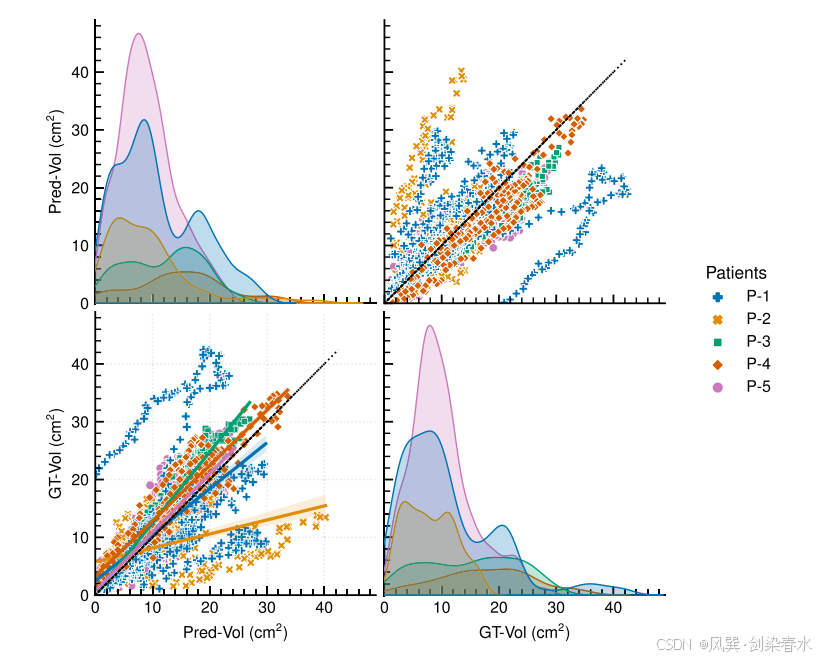

Figure 7 | 对每位患者的肿瘤生长进行预测评价,并在 GT-Vol 和 Pred-Vol 之间绘制配对图:图中的 identity line 表明 Pred-Vol 与 GT-Vol 的理想值相等,而 GT-Vol 和 Pred-Vol 的两种分布揭示了它们的相似性;